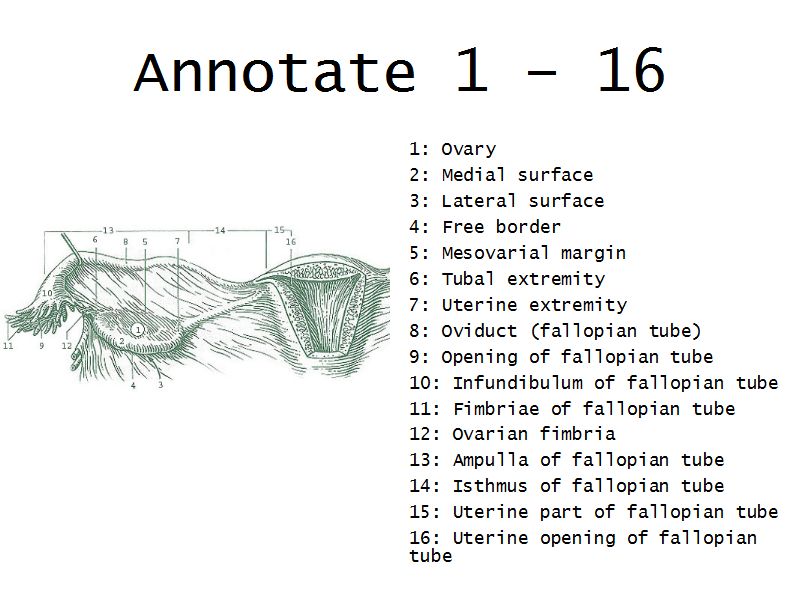

Tuba uterina

Slide 97

Also:

OviductFallopian tube

Uterine tube

Tuba uterina

- Muscular tube

- Most frequent site of fertilization

- Conveys zygote to uterus

- Four regions

- Three layers

Four regions

- Infundibulum

- Ampulla

- Usual site of fertilization

- Isthmus

- Pars interstitialis

- Passes through wall of uterus

Three layers

- Mucosa

- Muscular layer

- Serosa